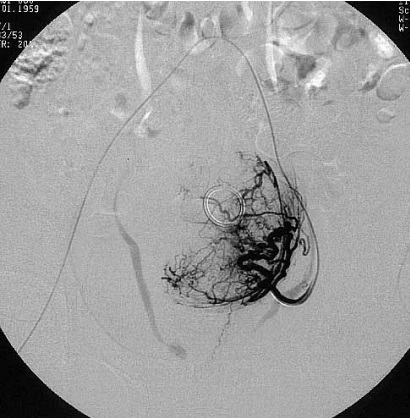

子宫动脉栓塞手术示意图

左子宫动脉栓塞术后肌瘤血供完全阻断